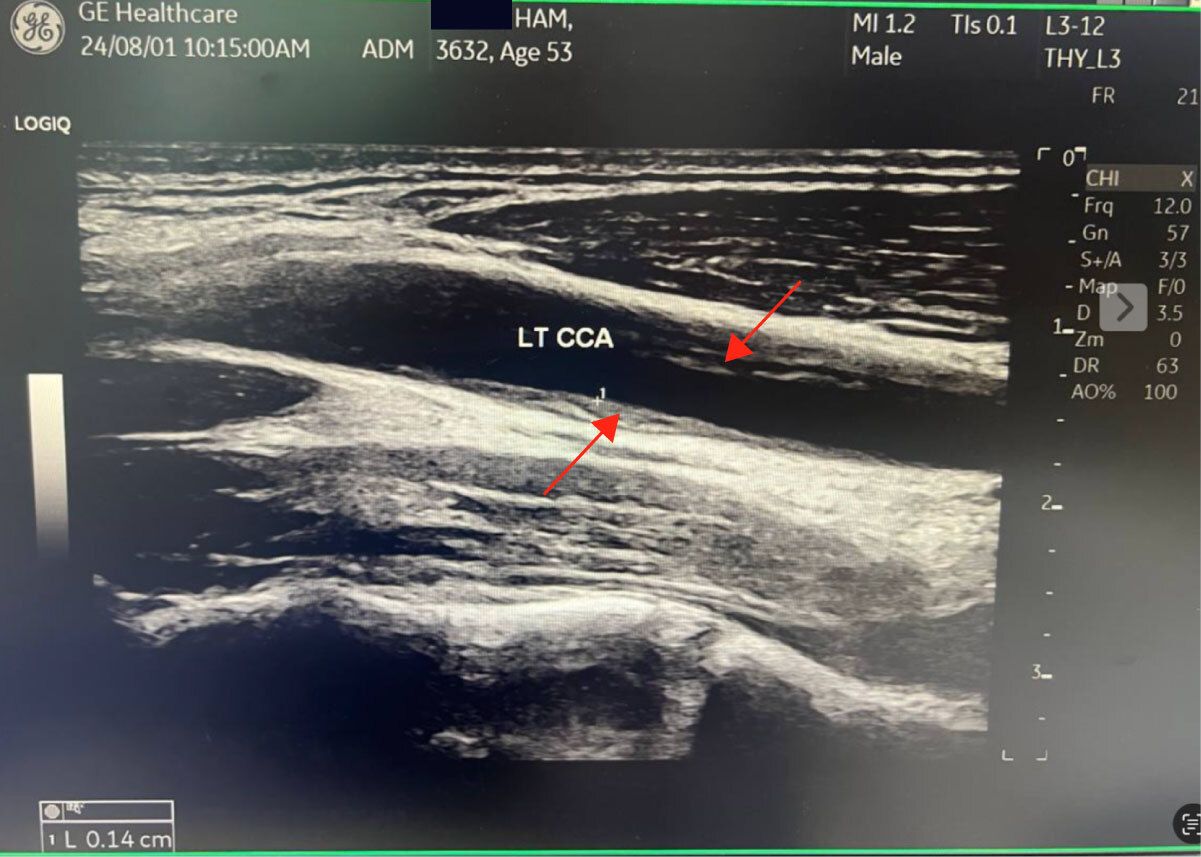

Look at my Left Carotid artery. See that plaque inside? It’s about 25% of the artery! This is from August 1, 2024. The ultrasonographer said I had more than usual for my age. I thought, “Yes, I knew I would have plaque.” Concerning. But what could I do? It was because of all the junk food I ate for decades when I was younger. I would just live a healthy life from now on, so it wouldn’t progress. I thought it wouldn’t be a problem until 20-30 years later, and functionally, it didn’t limit me at all. Boy, was I foolish!

This is a cross-section of my left common carotid artery. See the plaque in the middle of the photo? August 1, 2024. A year later, I reversed all this plaque and the thickening in my carotid artery wall, which you can see is marked at L 0.14 cm (1.4 mm), as measured by the Carotid Intima Media Thickness (CIMT) test.